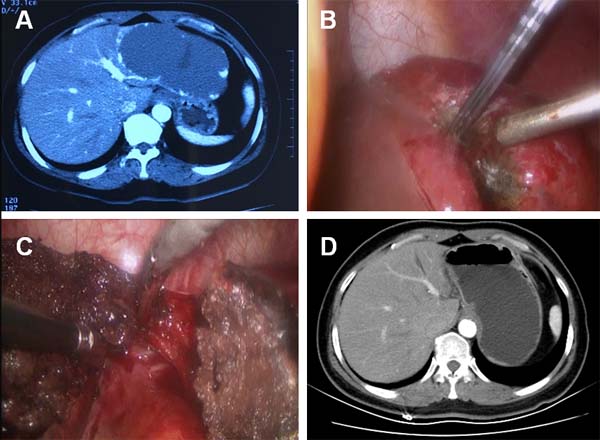

A 49-year-old female was admitted to our hospital for intermittent onset of vague upper abdominal pain for 3 months, which cannot be attributed to any specific reasons or relived by any medication. Abdominal ultrasonography detected a 12.0 cm mass in the lateral left lobe of the liver. The contrast-enhanced CT confirmed a hepatic hemangioma measuring 12.0 cm ×7.0 cm in diameters (Figure 1A). Upper gastrointestinal endoscopy and colonoscopy ruled out gastrointestinal diseases. Laboratory examinations, including routine blood test, biochemistry test for liver, renal and coagulation function and tumor markers didn’t show any abnormal findings. The patient had no history of chronic hepatitis or associated complications.

The resection margin was marked by diathermy on the surface of hemangioma about 1.0 cm away from boundary between the normal liver parenchyma and the tumor. RF-induced coagulation was performed along the resection margin by percutaneously introducing RF electrodes under direct visualization. We used internally cooled cluster electrodes, Cool-tip ACTC2025 electrodes and RF generator (Covidien Healthcare, Ireland) for the tumor coagulation. With a 2.5-cm exposed tip, the Cool-tip electrodes can produce ablation zones of 3.0 cm with a single placement of electrodes and a maximum power of 200 W in about 3-5 min. The tissue impedance was continuously monitored on the RF generator monitors throughout the procedure and the power output was adjusted accordingly. A sequential placement of RF electrode into the hemangioma along the resection margin was performed to achieve a complete coagulation of the tumor. A significant shrinking of the hemangioma indicates the complete coagulation of the tumor along the margin (Figure 1B). The hepatic hemangioma was dissected along the coagulation-marked resection margin using harmonic scalpel and a 1.0-cm band of coagulated hemangioma was untouched and left in place (Figure 1C). We removed the dissected tumor tissue using a surgical retrieval bag through the umbilical port and the tissue was analyzed by pathology. The coagulation time was 55 min and the tumor dissection time was 30 min. The total number of punctures was 8. Blood loss during resection was 100 ml. Hepatic cavernous hemangioma was confirmed by histology. The patient was discharged 6 days after surgery without any complications. The abdominal pain disappeared after surgery. Postoperative contrast-enhanced CT follow up showed there was no residual tumor one month after the surgery (Figure 1D). No appearances of late complications have been observed for 14 months since surgery.

Figure 1: CT and intraoperative photos of case 1. A. Contrast-enhanced CT demonstrated a 12.0-cm hepatic hemangioma located in the lateral left lobe of liver. B. Intraoperative photo showed the hemangioma at the resection margin shrank significantly after radiofrequency ablation. C. The hemangioma was removed and a 1.0-cm band of ablation-coagulated hemangioma was left in place. D. Contrast-enhanced CT showed that no residual tissue of the hemangioma exist in the tumor-dissected area.